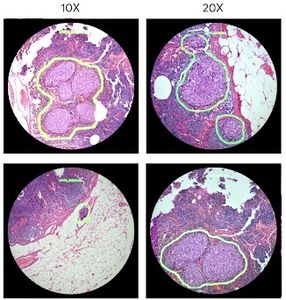

Verdächtig: KI markiert potenzielle Tumore (Foto: research.googleblog.com) |

Der aktuelle Prototyp kann so etwa zehn Bilder pro Sekunde bearbeiten, berichten die Forscher im Google Research Blog http://research.googleblog.com . Das sei ausreichend, um einem Pathologen optisches Feedback einzublenden, wenn dieser eine Probe unter dem Mikroskop bewegt oder die Vergrößerung verändert. Die Beispiel-Algorithmen umranden dabei Bereiche, in denen sie Tumore ausmachen, einfach grün, um die Aufmerksamkeit des Pathologen dorthin zu lenken. ARM könne aber auch anderes optisches Feedback bieten, wie beispielsweise Text, Pfeile oder Animationen.